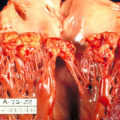

Myxomas typically appear as pedunculated masses in the left atrium on imaging.

Myxomas may causes syncope by blockage the mitral valve.

Metastatic cancers to the heart most commonly involve the pericardium, leading to a pericardial effusion.